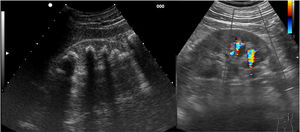

Ecográficamente las litiasis se observan como estructuras hiperecogénicas puntiformes o con forma de teja, con 2 artefactos ecográficos que apoyan el diagnóstico, la sombra acústica posterior y el artefacto centelleo con Doppler color (fig. 2 y video 3).

Se localizan en cualquiera de los cálices renales, en la pelvis renal, uréteres y vejiga. Son visibles con ecografía cuando son superiores a unos 4mm y son más fáciles de visualizar cuando se localizan en los calices o en la vejiga; y mucho más difíciles en el trayecto de los uréteres13.

Cuando una litiasis se desplaza hacia el uréter produce clínica compatible con un cólico renoureteral (dolor lumbar, náuseas, vómitos, …), y ecográficamente se observan signos de uropatía obstructiva, es decir, hidronefrosis o dilatación de la pelvis renal y/o los calices renales. Es en estos casos en los que hay que intentar determinar la localización de la litiasis que está produciendo la obstrucción. Con ecografía se localiza con facilidad si se encuentra en la pelvis renal o en el uréter distal, y es más difícil en el uréter medio por la interposición de meteorismo intestinal.